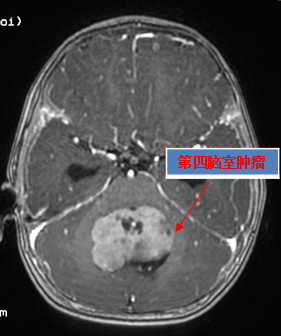

“当时我脚都软了,我很害怕,心里难受得不得了,自己好像没有了半条命。回去一个晚上都睡不着。”小蒙妈妈讲述起当天的情景时泪流满面。当地医院颅脑磁共振检查竟然发现小蒙脑内长了一个近6厘米的巨大髓母细胞瘤,由于当地医院不具备治疗条件,医生建议赶紧送往省城大医院手术。

“在比较短的时间,我们就给小蒙做了术前的准备,进行了多学科联合会诊。”神经外科主任陈陆馗说,“小蒙患的是恶性程度最高的髓母细胞瘤,体积很大,严重压迫脑干和小脑,已经导致明显的梗阻性脑积水。如果没有尽早发现并送医治疗,随着脑积水的进行性加重,颅内压越来越高,小孩随时都有可能突发呼吸停止、昏迷,严重时导致死亡。因此必须尽早实施开颅切除肿瘤,解除脑积水,降低颅内压力,才能挽救小蒙的生命。

“这是我院史上年龄最小的手术患儿,由于神经系统及心肺等重要器官的发育还未完善,进行麻醉和开颅手术难度极大、风险极高,术后重症管理要求极高,对主刀医生的技术和心理都是不小的考验。”陈主任解释道,“虽然神经外科团队对于小儿的开颅肿瘤切除手术已具有非常丰富的临床经验,但小蒙后颅窝容积比较小,髓母细胞瘤直接堵塞第四脑室,同时压迫脑干,肿瘤在桥脑和延髓的背侧,对桥脑和延髓的压迫很厉害。”为了万无一失、最大限度的确保患儿的手术安全,神经外科联合麻醉科、重症医学科(ICU)等进行多学科会诊讨论,做好围手术期准备,最大程度保障手术安全和疗效。